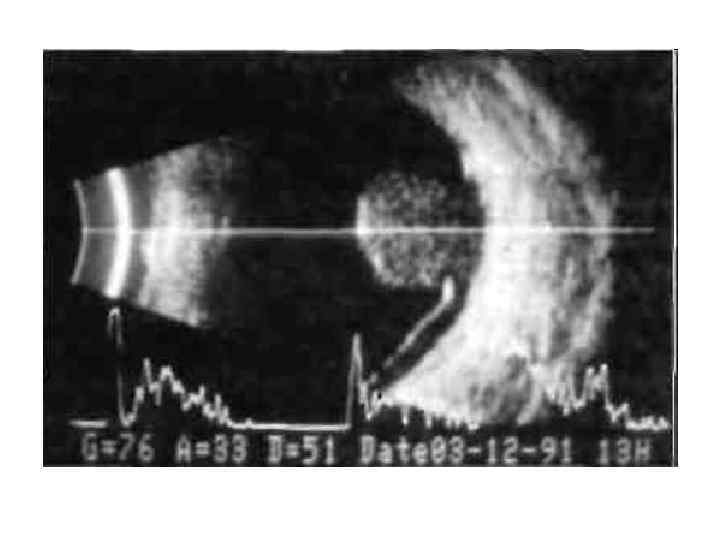

• Ультразвуковое исследование глаза

• Ультразвуковое исследование глаза